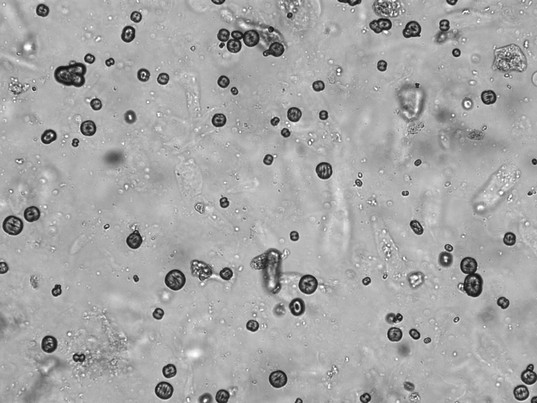

Während einfache Teststreifenanalysen nach wie vor ihren Platz in der Diagnostik haben, wird zunehmend auf automatisierte Verfahren zurückgegriffen. Diese ermöglichen es, große Mengen an Proben effizient zu analysieren und selbst kleinste Abweichungen zu erkennen. Diese neuen Technologien erleichtern die Arbeit im Labor, erfordern jedoch fundierte Kenntnisse, um die Ergebnisse korrekt interpretieren zu können. Die Befundung liegt bekannterweise nicht in den Händen der Labormitarbeiter – diese Kompetenz liegt bei den Ärzt*Innen. Die Aufgabe der Labormitarbeiter ist es aber, zu erkennen, um welche Bestandteile es sich im vorliegenden Harn handelt. Ein paar Fotos dieser Zellen werden hier nun gezeigt und benannt.

Unter diesem Text finden Sie ein paar Bilder eines Harnsediments. Um welche Zellen handelt es sich hier? Die Auflösung bekommen Sie in meinem elearning-Kurs.